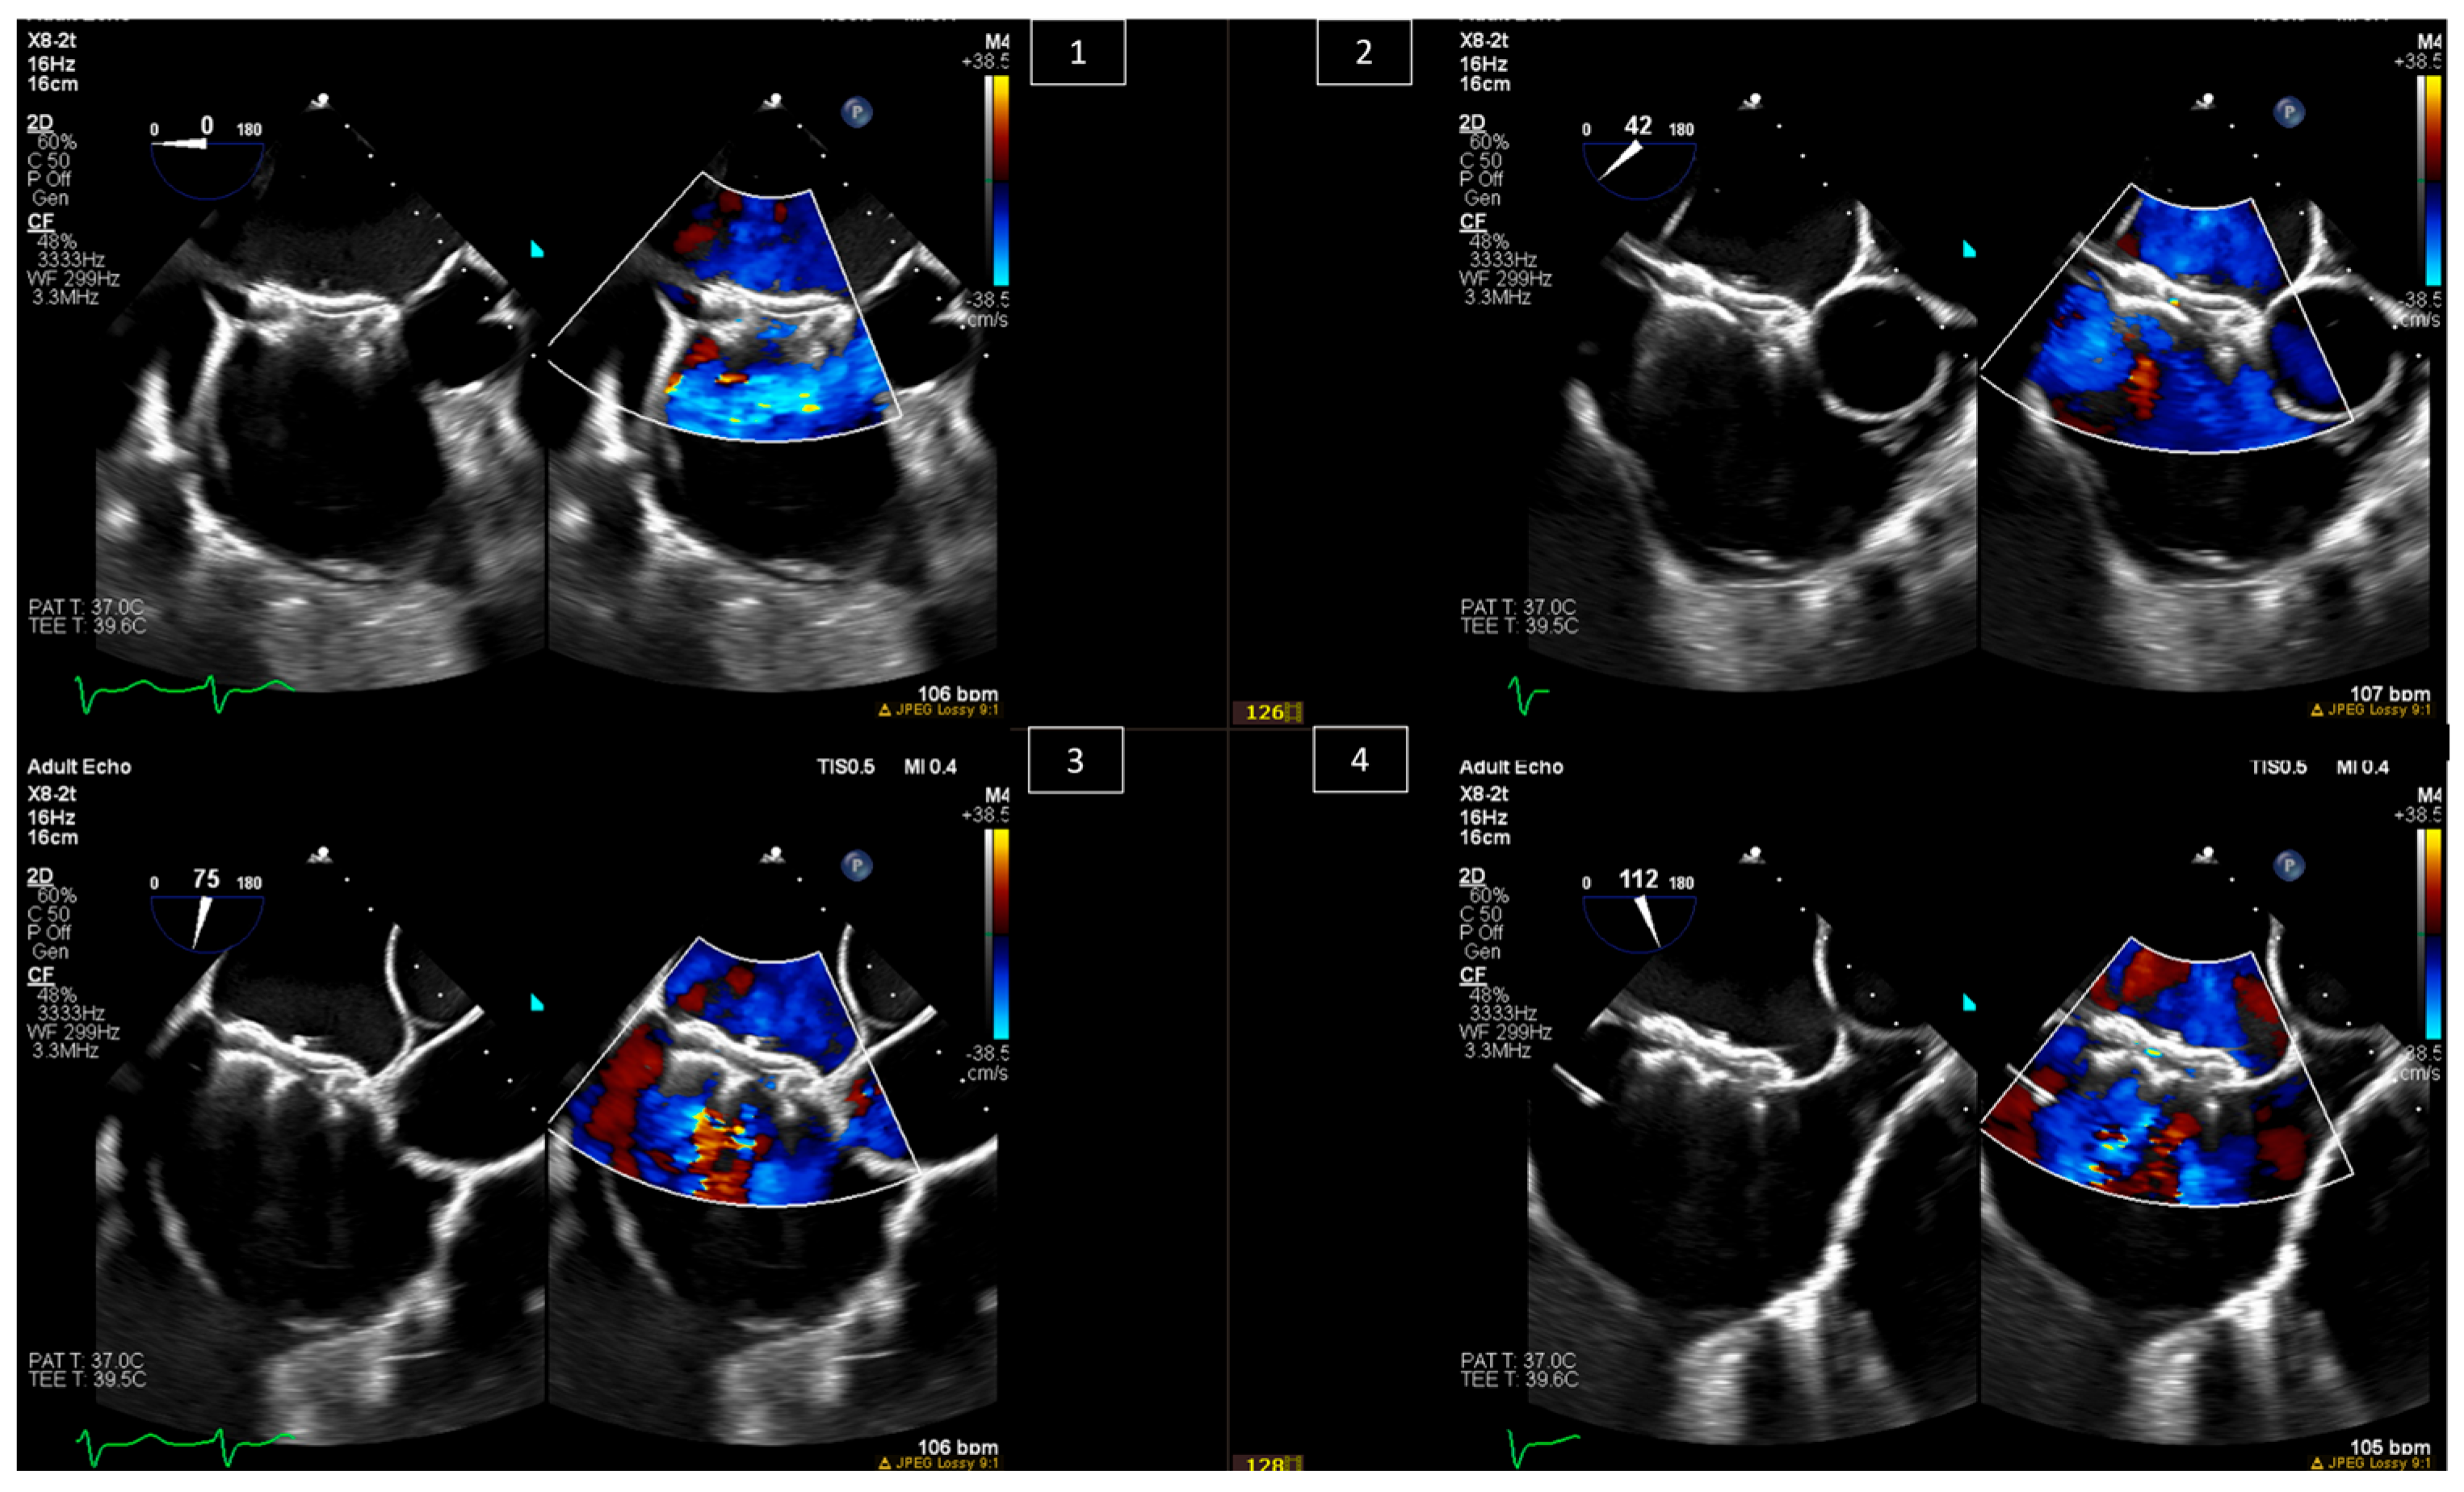

Highlights of Transesophageal Echocardiography During

Highlights of Transesophageal Echocardiography During